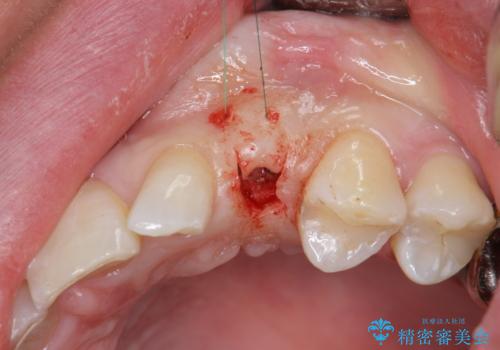

骨造成を伴う 前歯部インプラント治療

- 欠損している前歯のインプラント治療を希望され来院されました。

適切なインプラント埋入を行い、不足している骨量を補うため骨の造成を併用したインプラント治療を計画します。

前歯のインプラント治療は骨量・歯肉の厚み・インプラントの方向をしっかりと計画することで、審美的で長持ちを期待できるような仕上がりとなります。